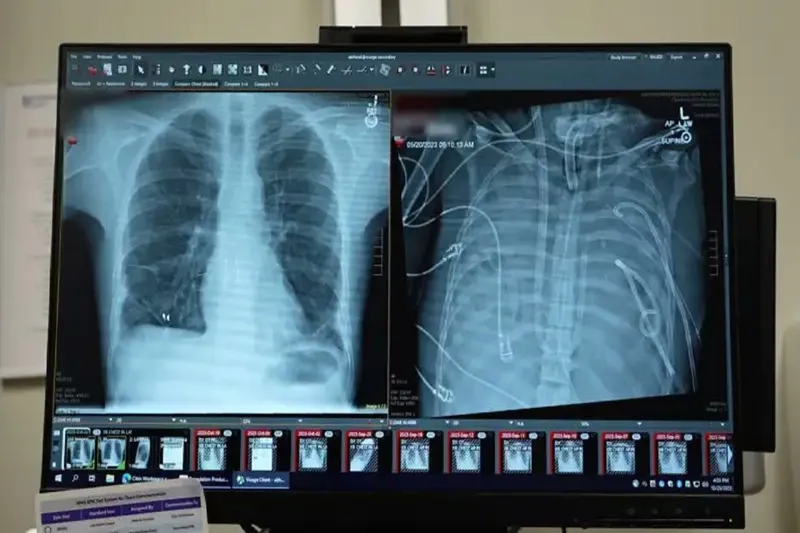

Yapay akciğer nakle kadar hastayı hayatta tuttu

Cerrahlar, akciğerleri geri dönüşü olmayan şekilde hasar gören bir hastayı, organ nakli yapılana kadar yapay akciğer sistemiyle 48 saat boyunca hayatta tutmayı başardı. Yeni sistemin, kalpten geçen kan akışını sürdürürken kana oksijen sağlayabildiği bild

Tıp dergisi Med’de 29 Ocak’ta yayımlanan çalışmaya göre, doktorlar kanı oksijenlendiren ve kalp dolaşımını destekleyen şantlar, tüpler ve pompalarla özel bir sistem geliştirdi. Uzmanlar, bunun gerçek anlamda bir yapay akciğerin, uygun donör bulunana kadar hastayı yaşatabileceğini gösterdiğini belirtiyor.

Olay, 2023 yılında Missouri eyaletinin St. Louis kentinde yaşayan 33 yaşındaki bir erkeğin influenza B virüsüne yakalanmasıyla başladı. Hastaneye kaldırılan hastaya, antibiyotiklere dirençli Pseudomonas aeruginosa bakterisinin neden olduğu ikinci bir enfeksiyon daha bulaştı. Enfeksiyon kana yayıldı ve bağışıklık sisteminin aşırı tepkisiyle birlikte akciğerler işlevini yitirdi.

Bharat, hastanın durumunun hızla kötüleştiğini belirterek “İyileşmiyordu. Aktif olarak ölüyordu.” dedi. Yapılan moleküler testler, hastanın akciğerlerinin kendiliğinden iyileşmeyeceğini ortaya koydu.

Bharat ve ekibi, COVID-19 ve diğer enfeksiyonlar sonrası akciğer nakli yapan bir merkez olarak biliniyor. Ancak hasta, aktif bakteriyel enfeksiyon taşıdığı için bu aşamada nakil olamıyordu. Aynı zamanda, ağır hasarlı akciğerlerle yaşamını sürdürmesi de mümkün değildi.

Bunun üzerine cerrahlar, hastanın hastalıklı akciğerlerini tamamen çıkararak geliştirdikleri yapay akciğer sistemine bağladı. Sistem, kalbin sağ tarafından alınan kanı bir pompadan geçirerek oksijen ekliyor ve karbondioksiti uzaklaştırıyor, ardından kanı kalbin sol tarafına yönlendirerek vücuda pompalanmasını sağlıyor. Böylece hem kalbin normal işlevi korunuyor hem de dokulara oksijen ulaştırılıyor.

Daha önce doktorlar, ekstrakorporeal membran oksijenasyonu (ECMO) adı verilen dış destek sistemini kullanarak, nakil bekleyen bazı hastaları akciğersiz olarak hayatta tutmuştu. Ancak Bharat, ECMO’nun kalp için yeterli kan akışını sağlamadığı için gerçek anlamda bir yapay akciğer olmadığını ifade etti.

Doktorlar, enfeksiyonun temizlenmesinin haftalar sürebileceğini öngörerek hastayı uzun süre bu sistemle yaşatmaya hazırlanmıştı. Ancak Bharat “Bakteri kaynağı olan akciğerleri çıkardığımızda enfeksiyonun çok hızlı şekilde gerilemeye başladığını fark ettik.” dedi.

Enfeksiyonun temizlenmesinin ardından hasta hemen organ nakli listesine alındı ve kısa sürede uygun bir donör bulundu. Aradan iki yıldan fazla zaman geçtiğini belirten Bharat, hastanın durumunun çok iyi olduğunu vurgulayarak “Kalbi normal, akciğeri normal. Hastanın durumu çok iyi.” ifadelerini kullandı. (İLKHA)